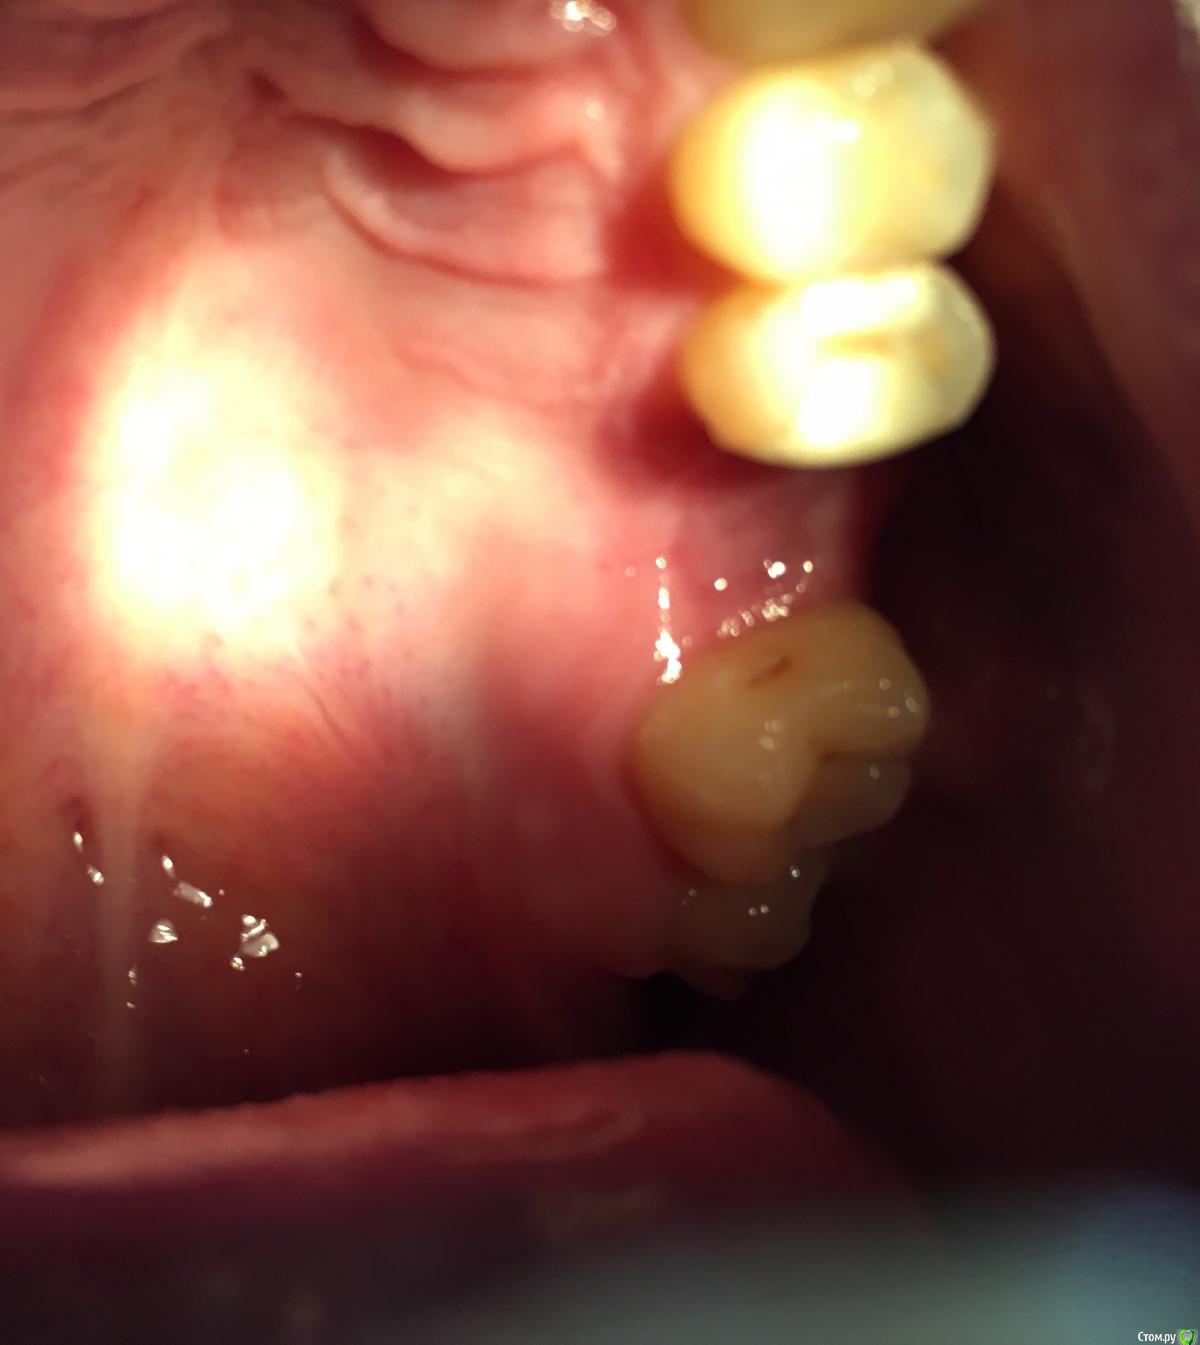

Bier Опубликовано 3 августа, 2018 Поделиться Опубликовано 3 августа, 2018 Точки болеть не могут, трогать их не нужно.Альвеолит может быть. Как лунка то выглядит? 1 Ссылка на комментарий

Павел10538 Опубликовано 3 августа, 2018 Автор Поделиться Опубликовано 3 августа, 2018 . Ссылка на комментарий

Павел10538 Опубликовано 3 августа, 2018 Автор Поделиться Опубликовано 3 августа, 2018 (изменено) Сфотографировал как получилось. Где то внутри какие-то жжения идут. Изменено 3 августа, 2018 пользователем Павел10538 Ссылка на комментарий

Bier Опубликовано 3 августа, 2018 Поделиться Опубликовано 3 августа, 2018 попробуйте небольшое зеркало найти и сфоткать отражение в нем. Вообще лунка вроде выглядит хорошо. 1 Ссылка на комментарий